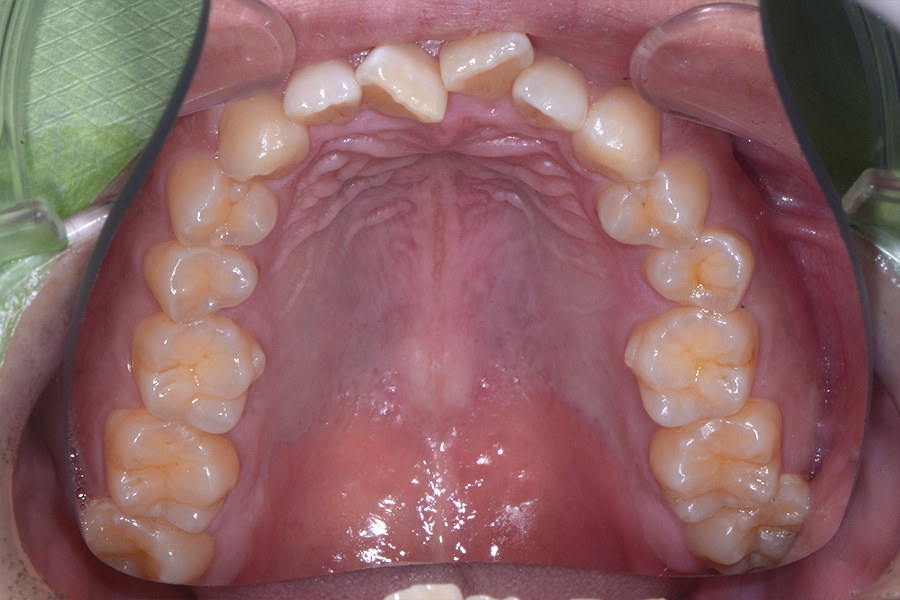

治療前

主訴 捻じれている歯を引っ込めたい

治療内容 上顎リンガル矯正(裏側矯正)